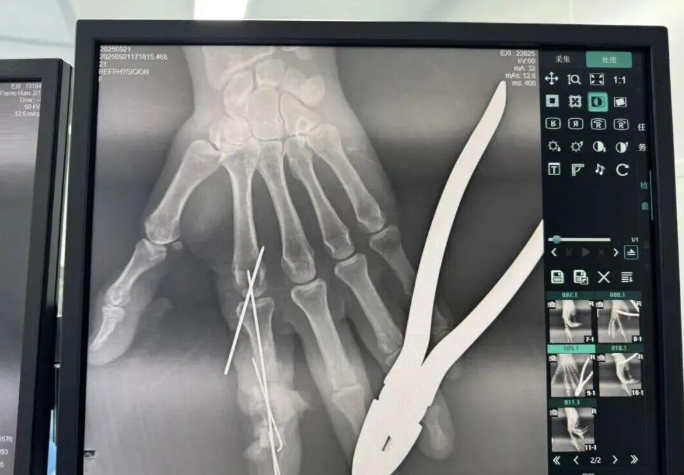

为确保手术成功,杨志主任特别联合刘金海主任组成多手术组协作团队,充分发挥梯队配合优势,反复研讨后确定了“组合式”手指再造方案:利用右足踇趾的皮瓣、末节甲床及部分趾骨,联合第二趾的趾间关节,再取部分髂骨进行精确植骨,将这些组织精密拼装,重建一个兼具良好外形和功能的新示指。

手术当天,多手术组梯队配合的优势得到充分体现。无影灯下,杨志主任与团队各司其职、紧密配合,一场漫长的生命接力就此展开。在放大40倍的专业手术显微镜下,医生们开始了精细操作。杨志主任在术后解释道:“患者需要吻合的血管直径仅0.5-1.0毫米左右,末节手指的毛细血管更是细如发丝。我们必须将移植组织与手部的血管、神经、肌腱进行精准吻合,确保移植组织通血成活。这不仅要求医生有扎实的显微外科技术,还要具备专业的整形外科审美能力,才能让再造的指尖既好用又好看。”

手术中团队发现,由于叶女士患有多年的内分泌系统疾病,其血管质量不佳,存在血管内膜分层、动脉顽固性痉挛等挑战。面对这一情况,团队及时启动应急预案。“每一根血管的吻合都不能有丝毫偏差,稍有不慎就可能出现血管内血流不畅,从而导致移植组织坏死。”杨志主任补充道。

手术中,医生们全神贯注,将纤细的血管像“绣花”一样逐一缝合,神经和肌腱的对接更是精准到毫米。这不仅仅是一场技术较量,更是一场对团队意志、耐心和体力的终极考验。